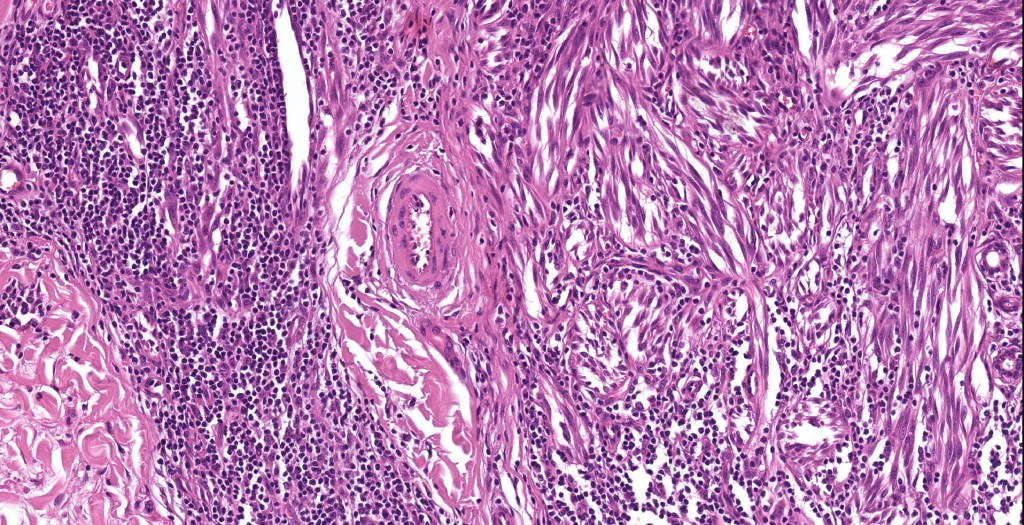

•Junctional nests often vertically orientated, dyscohesive with a surrounding retraction artifact

•Pleomorphism is almost invariable but affects all of the population to the same extent i.e., the cells & nuclei all look very much the same

•Spindle cell nests often display a “raining down” growth pattern

•Spindle cells have abundant cytoplasm and vesicular nuclei with small nucleoli

•Mitoses can brisk in younger patients and should not be taken as indicating melanoma

•Mitoses are restricted to the superficial aspect on the nevus and are never atypical

•Kamino bodies (often multiple) are a characteristic feature